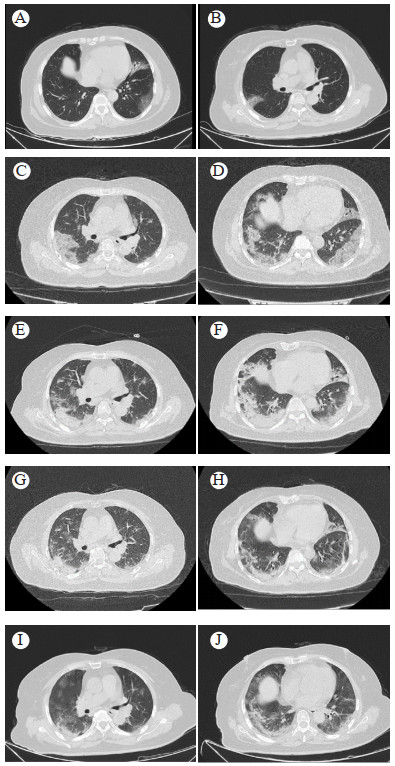

患者近1个月的治疗情况如下。07-30入住普通病房。查新型冠状病毒IgM抗体3.22 S/CO,新型冠状病毒IgG抗体29.01 S/CO。鼻拭子新冠核酸ORF1ab基因CT值23.00,N基因CT值19.00(内参CT值26.00)。血常规:白细胞3.95×109/L,中性粒细胞3.29×109/L,淋巴细胞0.94×109/L,血红蛋白136 g/L,血小板84×109/L;C-反应蛋白 < 10.0 mg/L,超敏C-反应蛋白8.42 mg/L。降钙素原(发光法)0.072 ng/mL,白介素6(发光法)32.68 pg/mL。生化检查示:丙氨酸转氨酶13.3 U/L,谷草转氨酶19.4 U/L,尿素5.40 mmol/L,肌酐59.1 µmol/L,乳酸脱氢酶297 IU/L,钾2.40 mmol/L,血糖5.18 mmol/L。胸部CT示:右肺上叶后段、左肺上叶前段、舌段及两肺下叶背段见片状磨玻璃影(图 1A、1B)。入院诊断:新型冠状病毒感染(普通型)、2型糖尿病、低钾血症。予吸氧、中药、俯卧位通气 > 12 h、依诺肝素钠注射液4 000AXaIU每日1次(qd)皮下注射、胸腺法新1.6 mg qd皮下注射治疗,及二甲双胍、急支糖浆、惠菲宁糖浆等对症治疗。08-02体温38.3 ℃、08-03体温39 ℃,各予散利痛1片口服。08-03 SpO2 85%(吸空气),肺部CT示两肺炎性病变较前进展(图 1C、1D),予经鼻高流量氧疗、新冠中和抗体BR-Ⅱ 198 1 000 mg静脉滴注。

| A:入院时中间支气管平面;B:入院时心室平面;C:住院第5天中间支气管平面;D:住院第5天心室平面;E:住院第11天中间支气管平面;F:住院第11天心室平面;G:住院第14天中间支气管平面;H:住院第14天心室平面;I:住院第22天中间支气管平面;J:住院第22天心室平面 图 1 患者胸部CT影像 |

08-04转入ICU。患者血糖持续波动在17.4~20.1 mmol/L,08-04加用瑞格列奈片(诺和龙)1 mg tid,08-08加用格列齐特缓释片(泰瑞欣)1片qd,血糖逐步控制在10 mmol/L。08-09胸部CT仍呈进展性改变(图 1E、1F)。08-12胸部CT好转(图 1G、1H)转到HDU,08-14改双腔鼻导管吸氧(3 L/min),仰卧位、俯卧位、吸氧活动后的SpO2分别为98%、99%、98%;08-18停止吸氧,仰卧位、俯卧位、活动后的SpO2分别为98%、98%、95%。08-20胸部CT提示病灶吸收,见图 1I、1J。